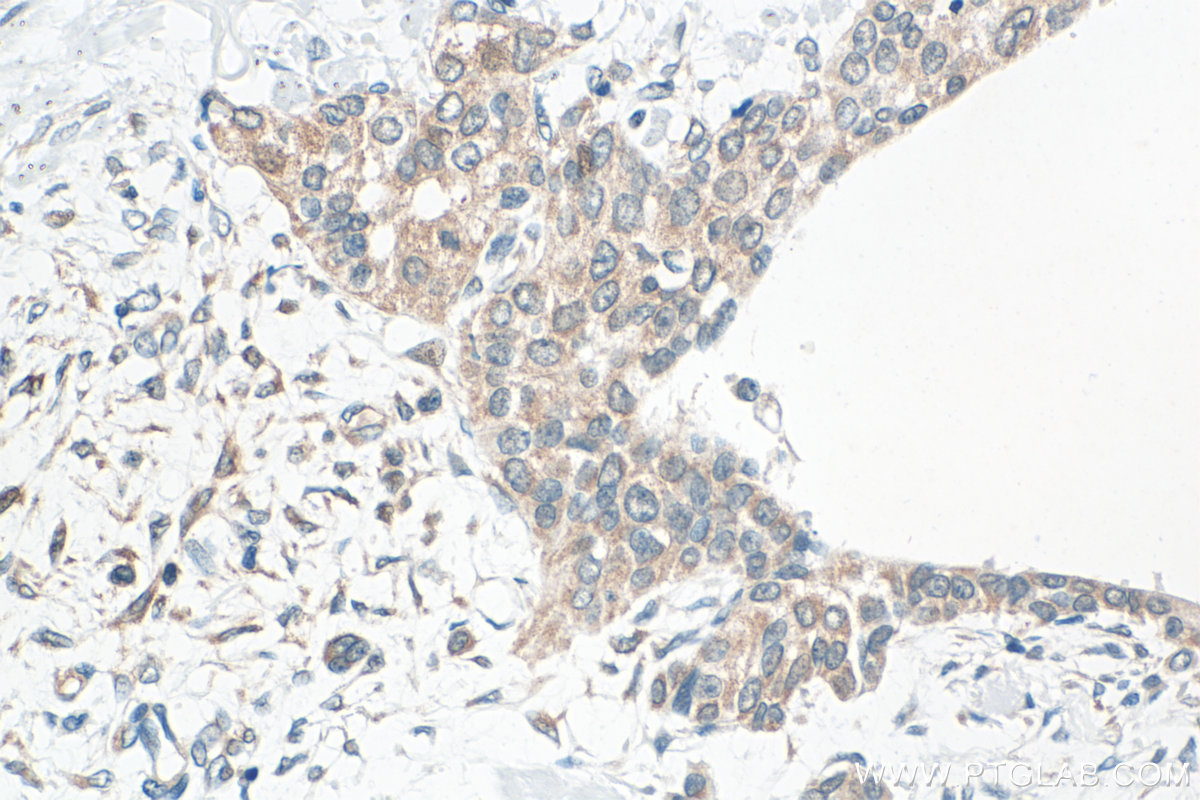

| Positive IHC detected in | human intrahepatic cholangiocarcinoma tissue, human urothelial carcinoma tissue Note: suggested antigen retrieval with TE buffer pH 9.0; (*) Alternatively, antigen retrieval may be performed with citrate buffer pH 6.0 |

| Immunohistochemistry (IHC) | IHC : 1:200-1:800 |